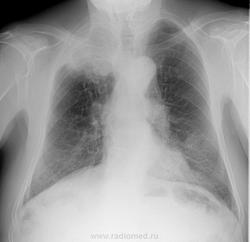

В передней проекции (в отличие от задней) первые ребра с обеих сторон тусклые. Добавляю флюорограммы обработанные программными фильтрами. Обратите внимание: в задней проекции первые ребра видны неплохо.

В 2006 году правильный диагноз не поставлен, но патологию НЕ пропустили. Вызывали на дообследование (даты на флюорограммах разные), посылали в ПТД… пошёл иль нет, бог весть… пропал на 5 лет (может быть и правда в среднюю полосу), пропала и амбулаторная карта. Летом 2011 г. уже с новой амбулаторной картой пришёл к неврологу с болью в правом плече, а от невролога на флюорографию грудной клетки и ШОП. Периферический рак лёгкого с синдромом Панкоста уже был почти очевиден и информация об этом отдана терапевту для передачи онкологу с рекомендацией дообследовать на КТ. Но терапевты менялись… пациент продолжал лечиться у невролога и хирурга, однократно сдал мокроту на ВК и трижды кал на я/глист… к онкологу попал только через 6 мес. От него направлен на рентгенограмму грудной клетки. Она есть у меня, но доделал цифровые флюорограммы. Они информативнее их и представлю.

Тут уже всё ясно. Синдром Панкоста во полном объеме. Картина патогномонична. Случай почти студенческий.